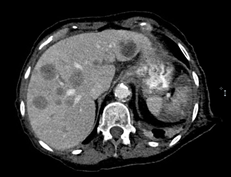

Abdominal Ultrasound for abdominal pain showed numerous hepatic lesions consistent with metastatic disease, confirmed by CT scan. CT scan of her chest revealed 1.5 cm spiculated nodule in the left upper lobe.